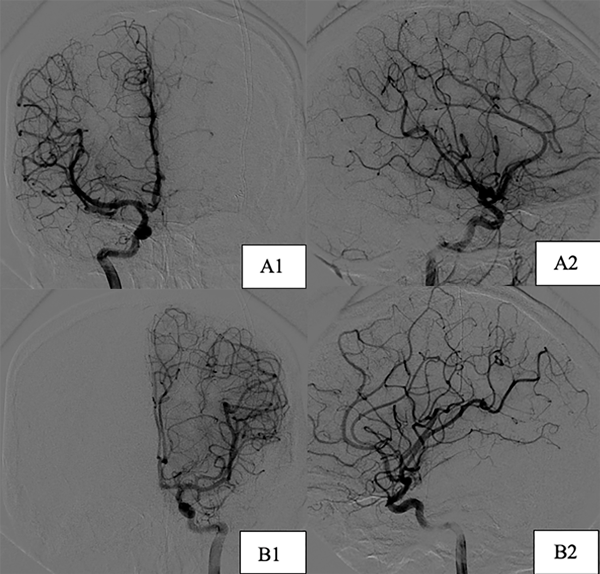

Inicialmente se realiza la gradación del riesgo quirúrgico de la MAV supratentorial según la escala de Spetzler Martin, siendo de bajo grado por su tamaño menor a 3 cm, su localización en área no elocuente y su drenaje venoso superficial (Grado 1), por lo que se decide su exéresis mediante microcirugía y 2 meses después se realiza clipado microquirúrgico de la lesión aneurismática incidental.

Un año posterior al primer procedimiento se efectúa nueva angiografía digital que no evidencia remanentes de la MAV tratada y correcta exclusión aneurismática (Figura 3), sin cambios respecto al tamaño de la MAV cerebelosa izquierda. Se decidió realizar embolización de esta debido a la negativa del paciente ante una nueva propuesta quirúrgica, pero por el reducido calibre de la arteria aferente no fue posible, decidiéndose finalmente su tratamiento mediante radiocirugía.

Figura 3. Imágenes postoperatorias caso 1, incidencias frente. A) Exéresis de MAV temporal derecha. B) Clipado de aneurisma de bifurcación carotídea izquierdo.